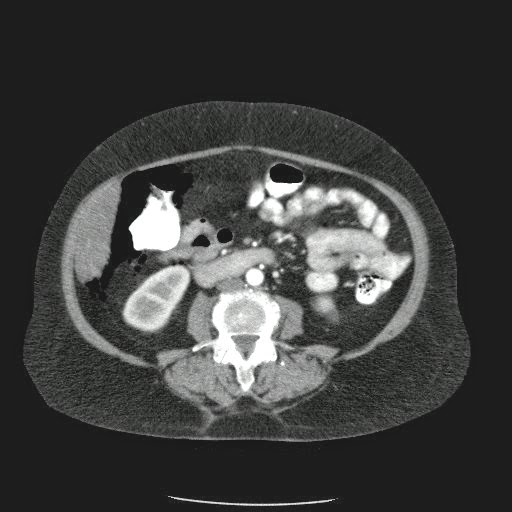

Caso Interesante #4

Adulto masculino, 1 semana de fiebre y malestar general.

¿Dónde esta ubicado el hallazgo?